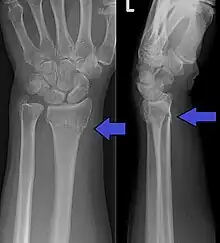

An X-ray showing a Colles' fracture

Colles fracture of the left hand, with posterior displacement clearly visible

Diagnosis can be made upon interpretation of anteroposterior and lateral views alone.[6]